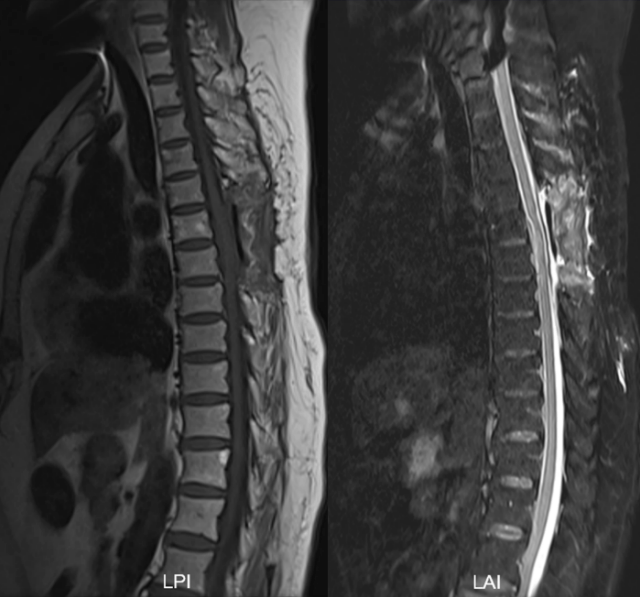

术后胸椎磁共振平扫(图3):术后明确病史,排除外伤以及医源性因素,最终